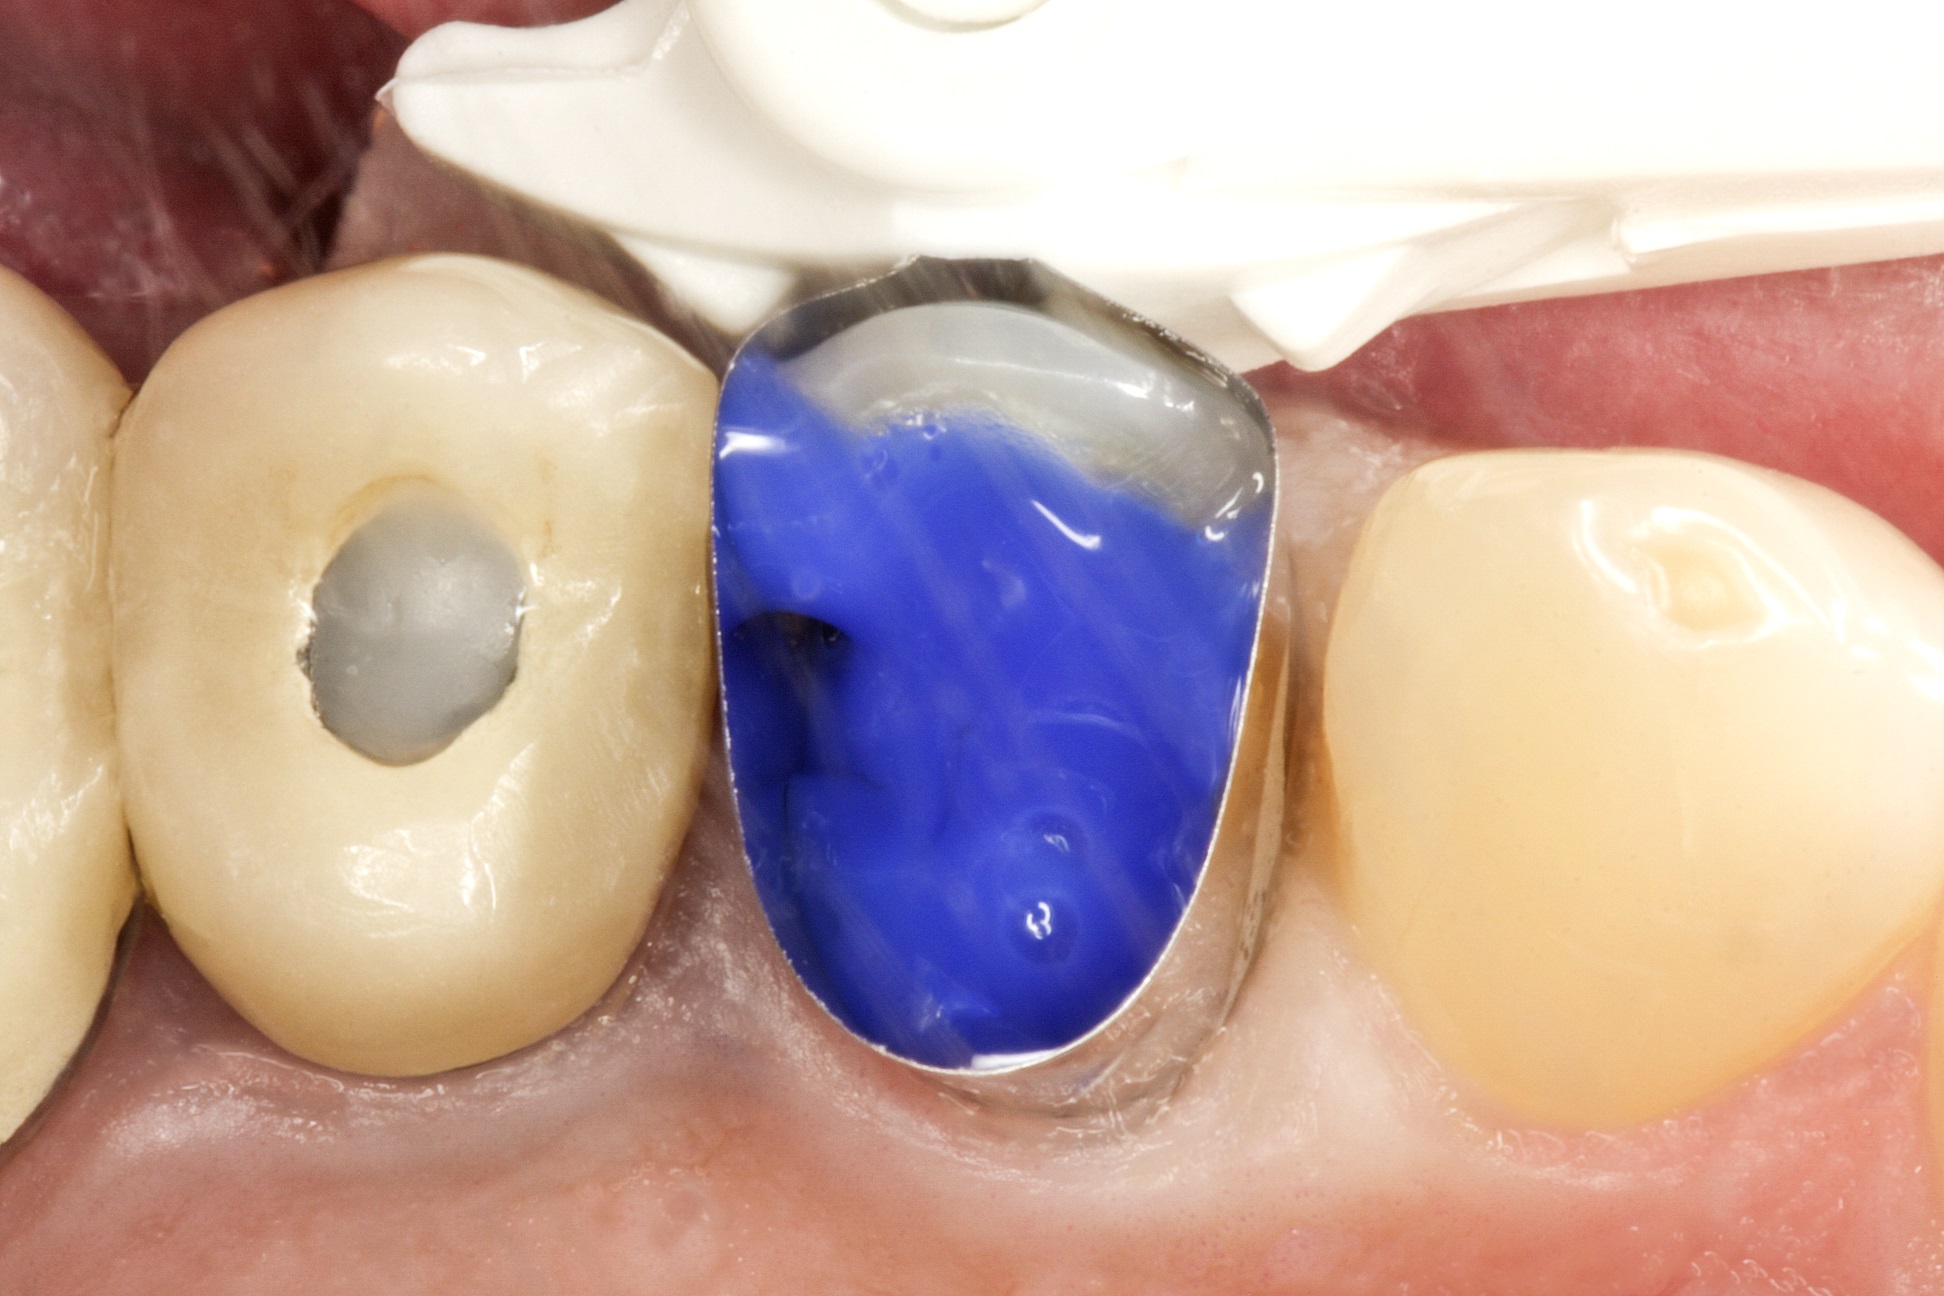

На зуб встановлюється одноразова матриця типу

Tofflemire (OmniMatrix, Ultradent). Весь підготовлений зуб протруюють

ортофосфорною кислотою протягом 20 секунд (рис. 4), а потім ретельно промивають

водно-повітряним спреєм. Після цього канали просушують паперовими штифтами.

Фото 4. Протруювання

зуба ортофосфорною кислотою.